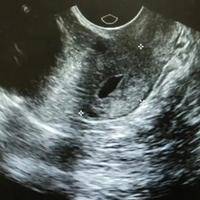

试管三级胚胎瑟吉欧质量相对较低的一类胚胎,通常表现为细胞分裂不均匀、外层细胞丧失或形成空泡等问题。很多患者在面对这种情况的时候,都不知道应该是直接冻还是养囊好一些,实际上,一般是建议大家选择养囊,这是因为养囊具有的优势是较多的。

1、激发胚胎潜能:囊胚培养可以激发不好的胚胎的发育潜能,在培养过程中有些异常的胚胎会自然淘汰,而有些质量好的会成功发育成囊胚;

2、与子宫内膜发育同步:囊胚在自然受孕过程中处于从输卵管到达子宫阶段和子宫内膜环境更加协调一致,在一定程度上增加了胚胎的着床率;

3、增加染色体正常率:人类卵子和精子中常常存在染色体异常的情况,这种异常往往是导致流产和先天性畸形的主要原因。通过养囊技术,可以筛选出形态和染色体正常的囊胚进行植入,从而降低染色体异常引发的问题;

4、降低宫外孕几率:在囊胚移植后,通常1-2天便会进行着床,相比于不养囊来说,着床时间明显缩短,降低了宫腔外着床的几率,从而也就降低了宫外孕的几率;

5、提高胚胎着床成功率:对于做试管的女性患者来说,试管促排以及取卵都可能对女性身体造成一定的伤害,女性选择养囊,就有充足的时间调理身体,让身体恢复到状态,能够提高胚胎移植成功率。

综上所述,试管三级胚胎养囊具有诸多好处。当我们培养出一个质量相对来说较差的胚胎的时候,也不要灰心丧气,此时选择养囊还是有成功的希望了,当然了,具体选择何种的治疗方式,还是要根据医生的建议来做最后的选择。